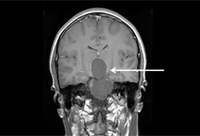

Meningioma: imagem coronal aumentada com contraste demonstra meningioma no seio cavernoso no lado esquerdo

Da coleção pessoal de William T. Couldwell; usada com permissão